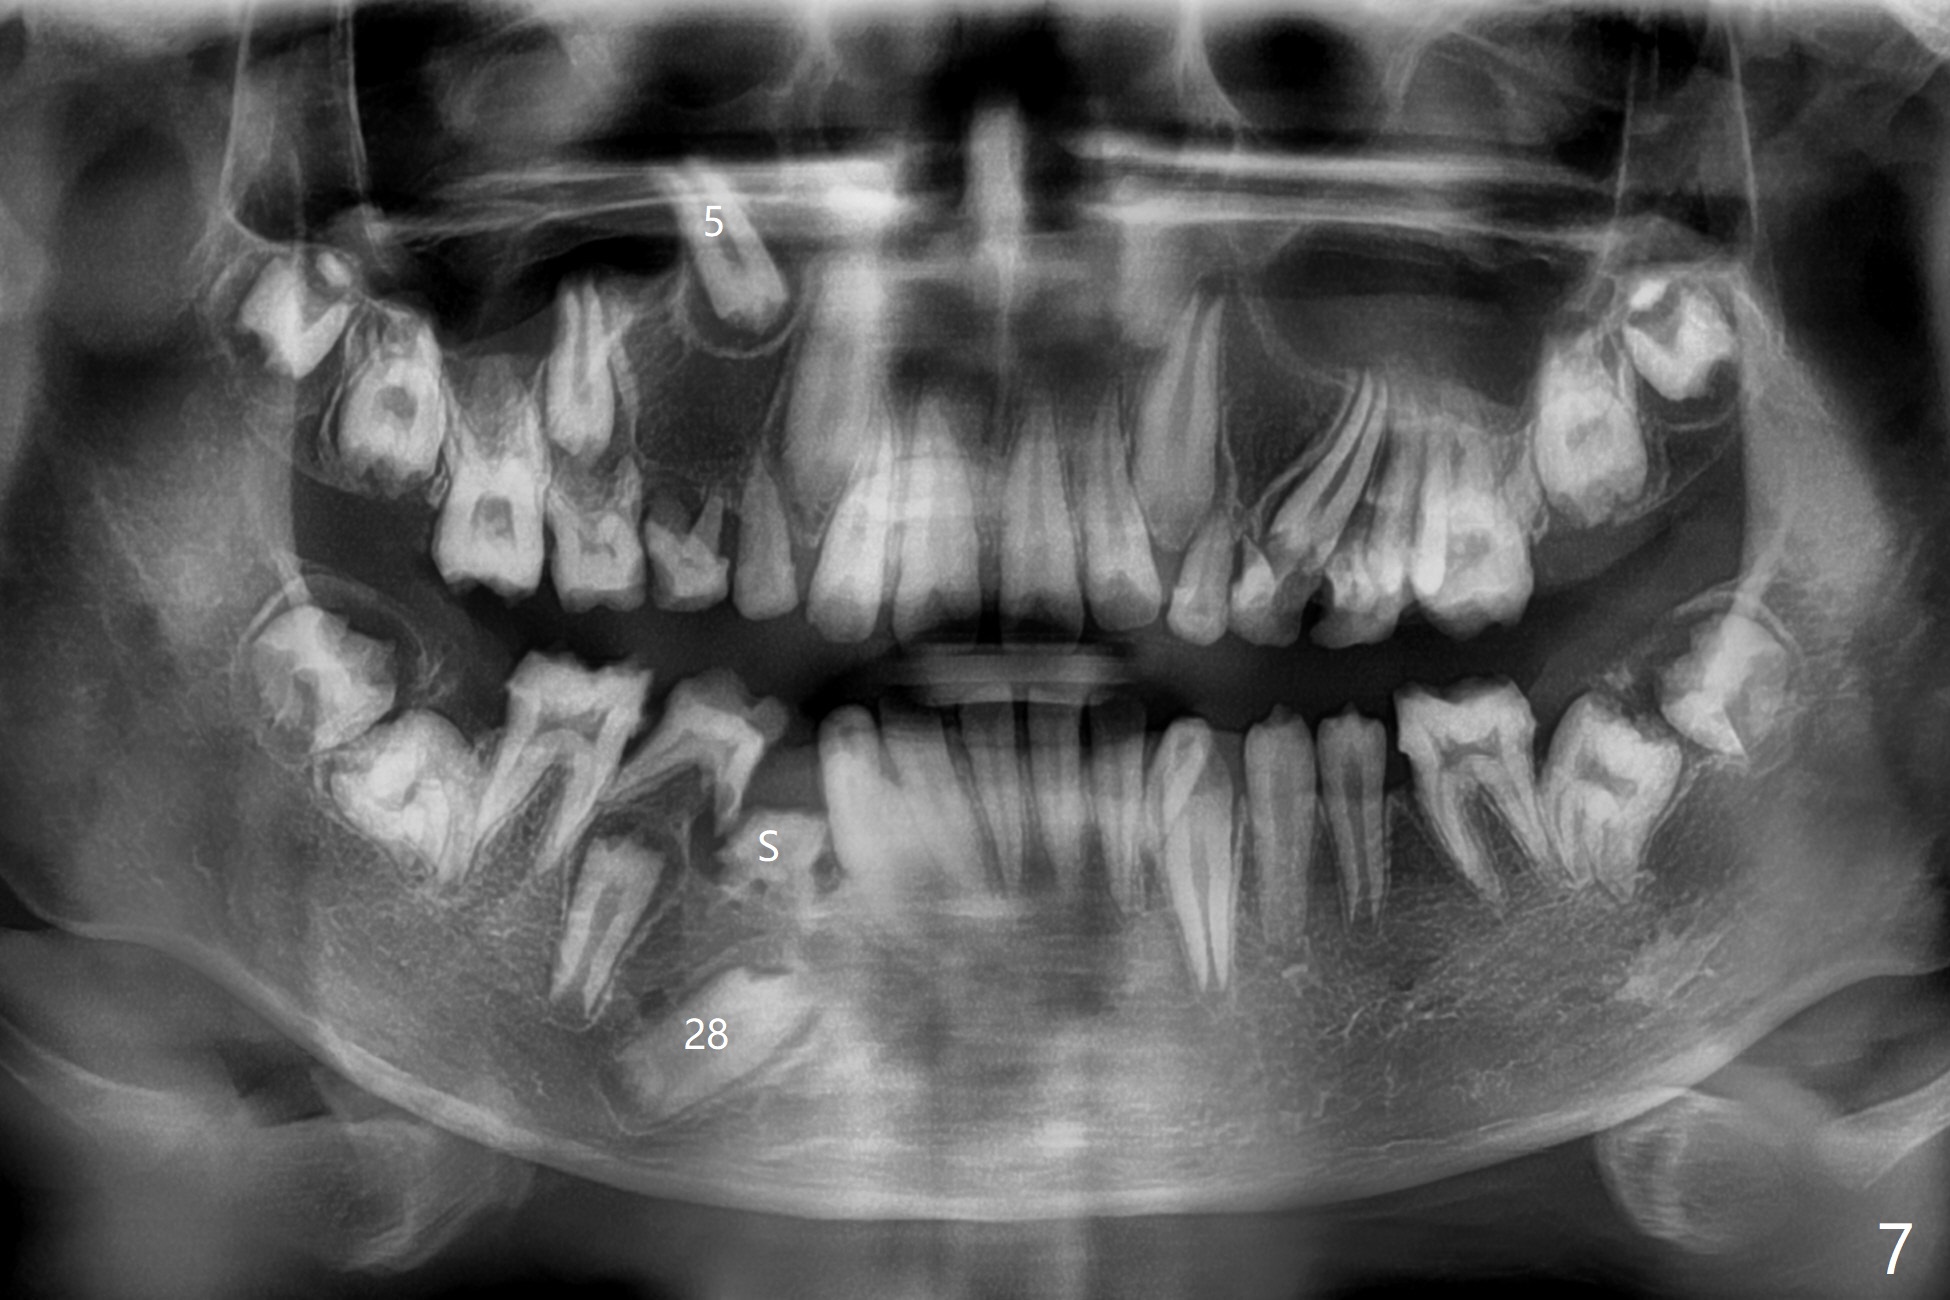

13岁男孩,每颗乳恒牙交换时乳牙都需要拔除,萌出的恒牙个子小,侧切牙反合(图二,五),对冷热敏感,不爱刷牙,口腔卫生欠佳(图三:13(结石)),父母要求诊治。今天在局麻下,左上洁治,没有局麻区域无法洁治,敏感,并且拔除H-J。S下沉,5,28埋伏(图七),其余乳磨牙都有龋齿。如何治疗?是釉质发育不全?暴露5,28前将拍摄CT。